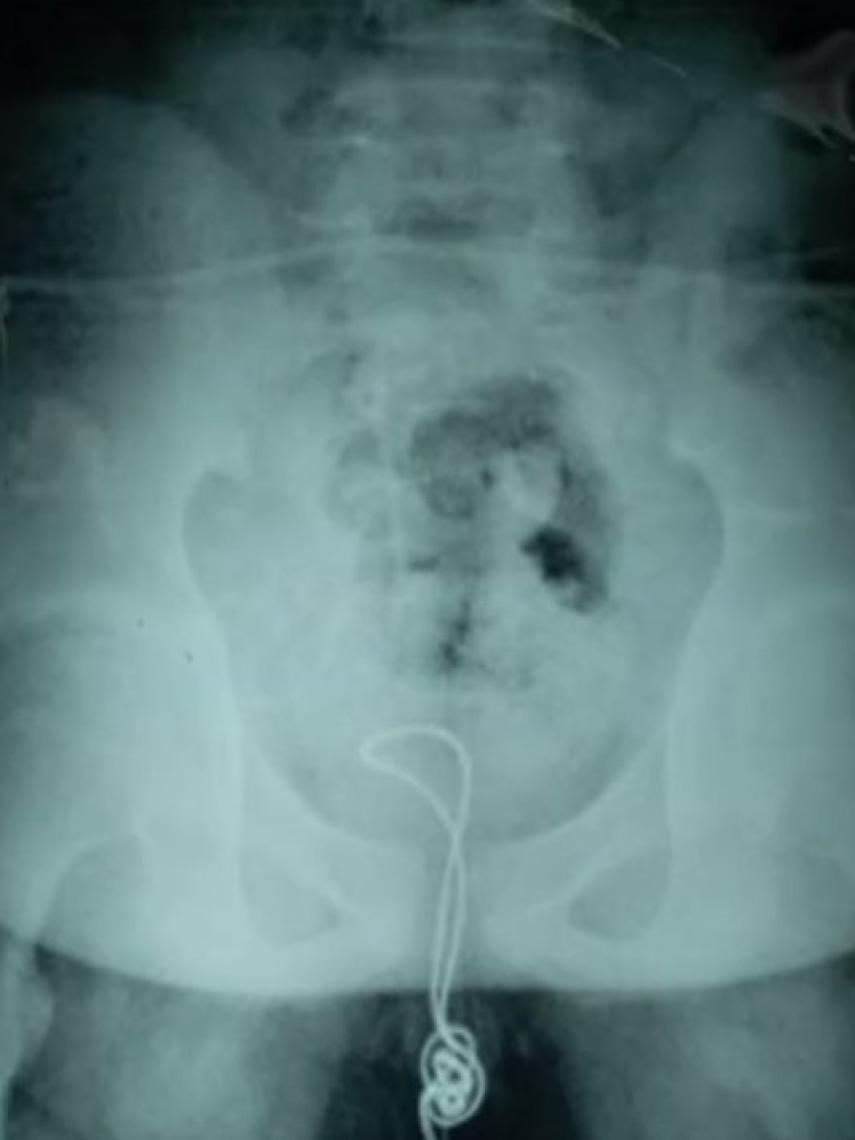

Y es que por alguna razón un adolescente taiwanés de 13 años decidió que sería buena idea conectar un USB a su pene ¿querría comprobar si se cargaba? Pero no se limitó a la puntita, sino que se metió 20 centímetros de cable por la uretra hasta tocar con la vejiga. No sabemos las dificultades que encontró al introducírselo -fácil no tuvo que ser- pero su drama comenzó cuando intentó extraerlo y se topó con que no podía sacarlo. Momento en el que tomó la sabia decisión de ir al médico.

En el hospital local trataron de extraerlo aplicando lubricante pero fue imposible, por lo que lo transfirieron al Hospital Infantil de Harbin al día siguiente. Allí descubrieron el problema: el chico había cortado la cabeza para introducirlo, al llegar hasta la vejiga, se lió y acabó formando un nudo -como los auriculares en el bolsillo, pero en su sistema urinario-.

Situación ante la cual los médicos no tuvieron más remedio que operar, cortar el cable para extraer el nudo y sacar el resto del cable de la misma forma que había entrado. El chico fue dado de alta dos semanas después de pasar por el quirófano con sus partes en perfecto estado. Según aseguró, sentía "curiosidad" por su cuerpo, por lo que envió una sonda a los abismos de su organismo.